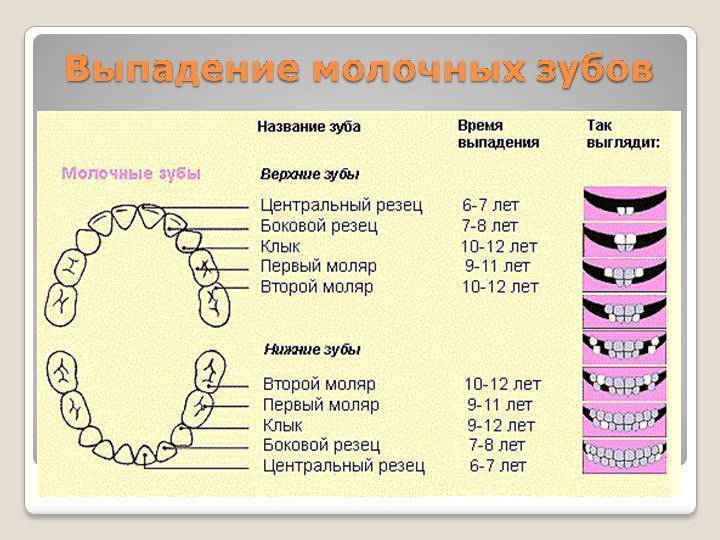

Приблизительная очередность выпадения и смены зубов:

Возраст ребенка Зубы

6 – 7 лет – Нижние, а за потом верхние центральные резцы, первые моляры

7 – 8 лет – Боковые резцы

9 – 10 лет – Первые премоляры

10 -11 лет – Прорезывание клыков, вторых премоляров

11 -13 лет – Вторые моляры

В большинстве случаев зубы, находящиеся снизу, выпадают раньше, чем соответствующие им резцы, клыки или моляры, находящиеся в верхней челюсти.

Молочные зубы у детей: схема выпадения

Выпадение начинается с резцов и далее в том же порядке, что и их прорезывание. В норме выпадать зубки у ребенка должны согласно следующему графику:

- Центральные резцы выпадают к 6-7 годам.

- Вторые резцы начинают выпадать к 7-8 годам.

- Первые моляры выпадают к 10 годам.

- Клыки и вторые моляры к 12 годам также заменяются на постоянные.